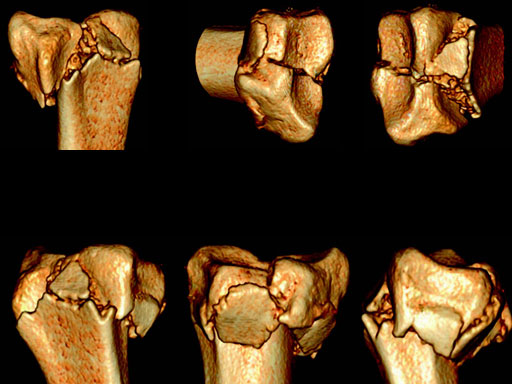

Fig 2af Preoperative 3-D CT scans.